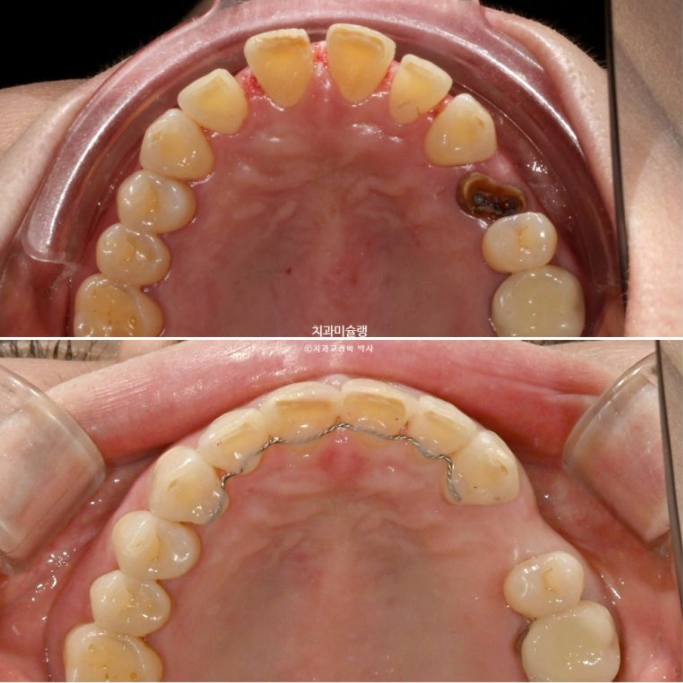

24.07

24년 7월 50대 환자분께서 교정치료를 위해 오셨습니다.

앞니가 세로 길이보다 가로길이가 더 긴, 한마디로 납작한 형태입니다.

치아 사이사이 벌어진 틈을 레진으로 메꿔놓고 지내온 것입니다.

충치로 인해 어금니들을 발치하게 되면서 교정치료를 병행하고자 오셨습니다.

일단 앞니 사이사이 레진을 제거해 보았습니다.

아래 앞니 사이 치석도 같이 제거합니다.

레진이 차지하는 비중이 컸습니다

아래 앞니 사이사이는 공간이 없는 데 위 앞니 사이사이에만 큰 공간이 있다면

이 공간을 교정으로 100% 메꿀 수 없습니다.

최대한 공간을 줄여놓고 남은 미세공간은 레진으로 마무리 해야 합니다.

인비절라인 라이트 치료 권유드렸습니다.

아래 앞니는 원래 있던 블랙트라이앵글을 없앨 겸 치간삭제를 동반하기로 합니다.

또한 아래 앞니가 위 앞니를 밀어내어 위 앞니 벌어짐이 심해지지 않도록 아래 앞니는 함입도 필요합니다.

26년 1월 마지막 장치를 다 끼고 남은 공간을 레진으로 메꾸기로 합니다.

26.01

레진치료 직후 모습입니다.